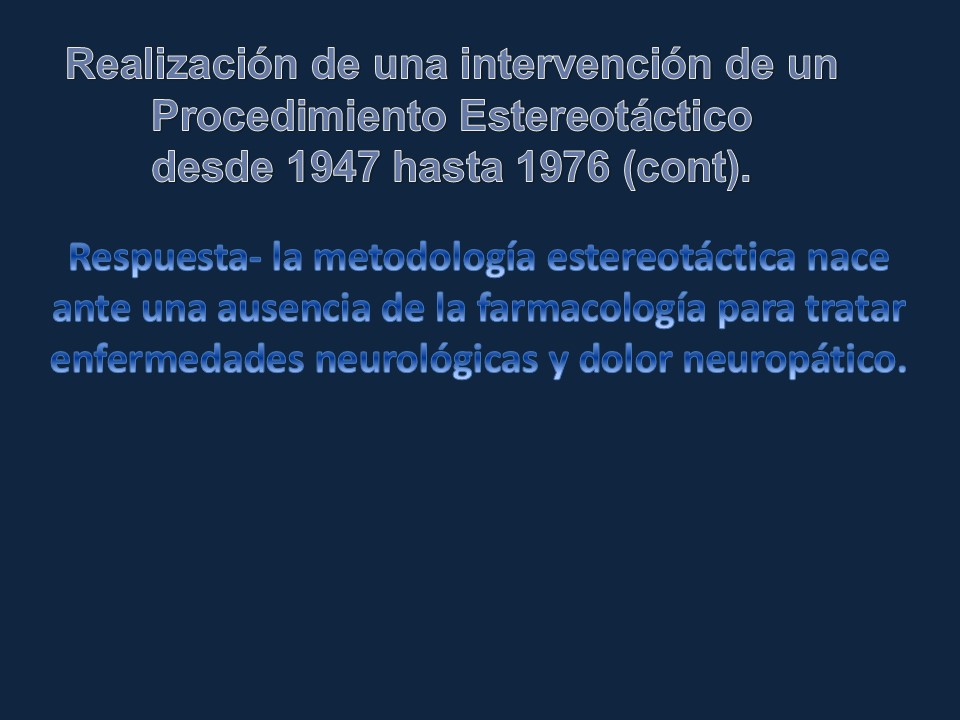

Metodología Estereotáctica o Estereotaxia

Dr. Guillermo Larrarte